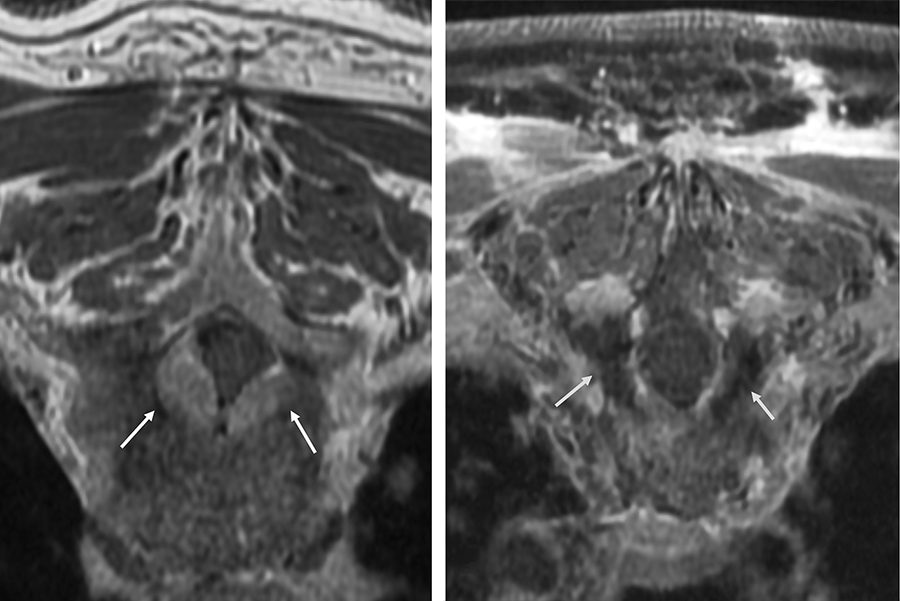

Termoterapia intersticial inducida por láser para metástasis vertebrales

La técnica láser puede ser una alternativa a la cirugía abierta antes de la radioterapia estereotáctica para metástasis adyacentes a la médula espinal